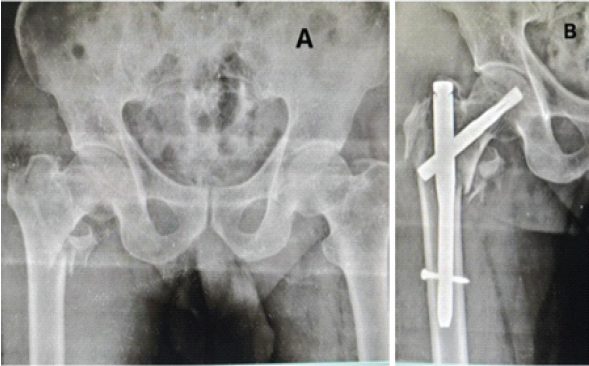

A 60-year-old male patient with TYPE 31-A2.2 pertrochanteric femur fracture of the right side (Fig. 4).

Figure 4: (a) Pre-operative anterior-posterior (A-P) view X-ray showing TYPE 31-A2.2 pertrochanteric femur fracture of the right side. (b) Post-operative A-P view X-ray showing pertrochanteric femur fracture fixed with short proximal femur nail.